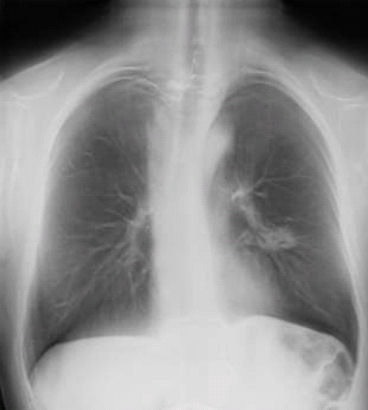

Italian researchers presenting at this week's European Lung Cancer Conference (ELCC) in Geneva believe that digital chest tomosynthesis could eventually become a "mammogram for the lungs" by enabling lung cancer screening of high-risk individuals -- at a lower cost than CT.

Researchers from S. Croce e Carle Hospital in Cuneo, Italy, presented a paper that details their experiences in screening more than 1,800 current and former smokers with a digital tomosynthesis unit, a specially adapted digital radiography (DR) system with a tube head that pans around the patient, collecting multiple image acquisitions. The system achieved a lung cancer detection rate on par with recent clinical studies based on low-dose CT screening.

Results presented at both meetings have led the researchers to postulate that digital chest tomosynthesis could eventually be used as a sort of triage tool for chest screening of high-risk individuals, with suspicious or more complex cases referred for further examination with low-dose CT.